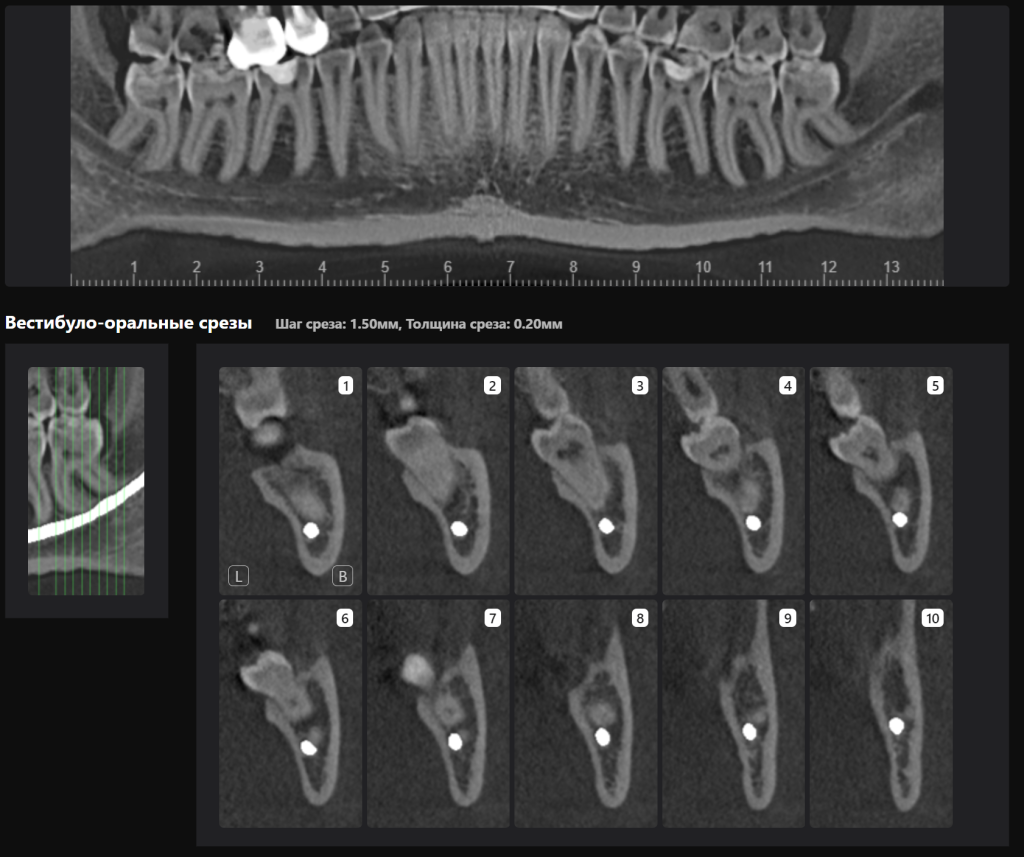

«Отчет по третьим молярам», созданный ИИ Diagnocat — это инструмент, который проводит точный трейсинг нижнечелюстного канала

И выстраивает оптимальную визуализацию в трех плоскостях и помогает врачу оценить расстояние до нижнечелюстного канала

Зубы 3.8 и 4.8 удалены с минимальной хирургической травмой без повреждения нижнего альвеолярного нерва